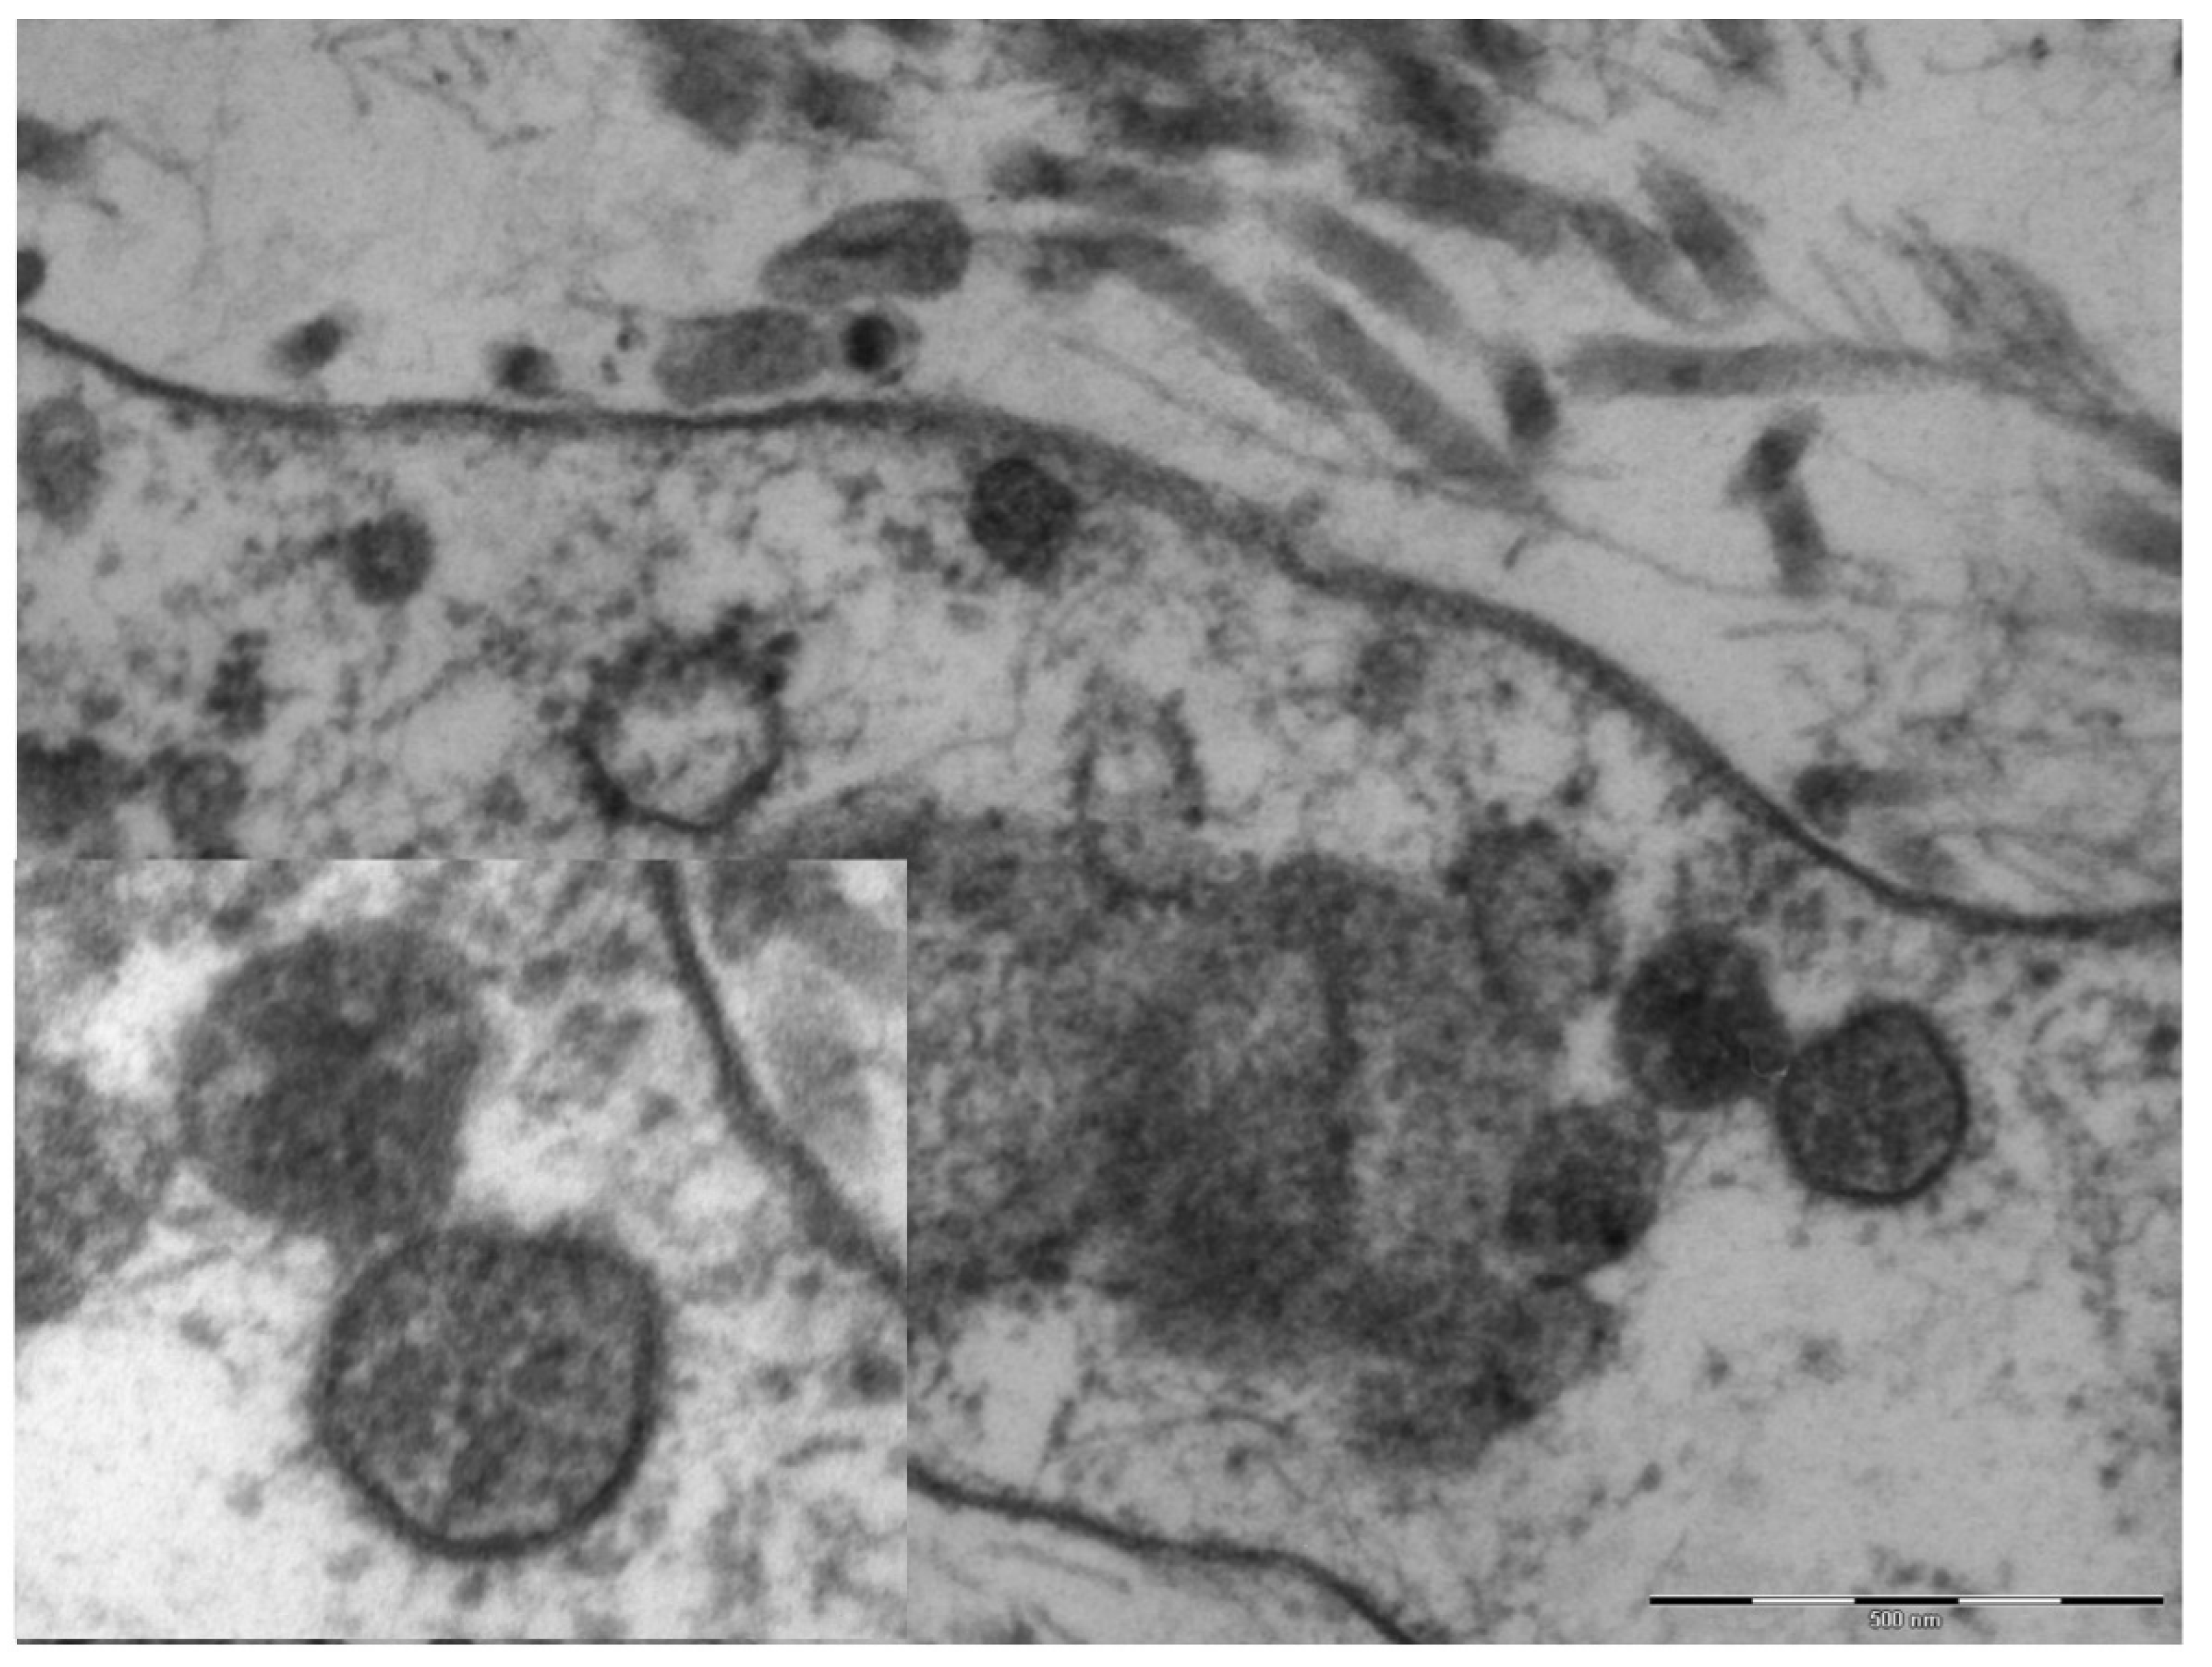

An electron microscopy study was performed in only one case, showing marked hypertrophy of the endothelial cells, the nuclei being characterized by finely distributed chromatin and retiform nucleoli. The cytoplasm contained very few organelles, with few small globular mitochondria. The fibroblasts were remarkably elongated and surrounded by very short collagen fibers. Spherical structures ranging from 65 to 136 nm were visible in the cytoplasm of endothelial cells and fibroblasts (Figure 4), characterized by a peripheral electron-dense rim and a clearer core. These structures were more frequently near the cell membrane or externally attached to it. Aggregates of multiple viral particles were grouped together close to phagosome-like vesicles. In some images, faintly electron-dense projections of different sizes (6–10 nm)—corresponding to the virus spikes—were visible, depicting a solar crown.

Figure 4.

Original magnification 89,000× fibroblast cytoplasm containing numerous maturing coronaviruses. Fragmented collagen fibers are visible in the interstice. In the box, 110,000×, whole virions are evident with spikes of different lengths and an electron-dense peripheral rim.